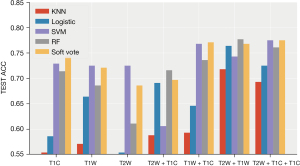

- Plan A (I + II): (see Table 2, Figure 6)

RF showed the best performance, reaching the highest average accuracy rate of 0.777 (0.738, 0.815) and AUC of 0.808 (0.769, 0.848) on the T2W + T1W sequence. The performance of the classification model and SVM after the integration of the two strong classifiers was slightly lower than that of the RF, and both reached the highest average accuracy on the T2W + T1W + T1WC sequence: ACC: 0.775 (0.755, 0.795), AUC: 0.752 (0.7, 0.803) and ACC: 0.775 (0.745, 0.805) AUC: 0.754 (0.687, 0.83). Compared to the other sequences, the T2W sequence had better effects on different classifications.

- Plan B (I + III): (see Table 3, Figure 7)

The classification model integrated by two strong classifiers showed the best performance, reaching the highest average accuracy rate of 0.789 (0.763, 0.816) and AUC of 0.659 (0.583, 0.735) on the T2W + T1W + T1WC sequence. Performance was relatively stable, and the accuracy rate was higher than 70% in the seven sequence combinations. Following a RF, the average accuracy rate reached 0.782 (0.741, 0.823), and the AUC reached 0.733 (0.667, 0.799) in the T2W + T1W sequence. The results of the nearest neighbor and logistic regression models are not ideal, especially the nearest neighbor algorithm.

- Plan C (I + II + III): (see Table 4, Figure 8)

After combining the key features of the different sequences, the performance of the three sequences was greatly improved in the integrated classification model [ACC: 0.796 (0.76, 0.833), AUC: 0.689 (0.615, 0.763)]. The average accuracy rate was close to 80%, and the average AUC exceeded 70%. Furthermore, the performance was stable, and the accuracy rate was higher than 70% in multiple sequence combinations.

After the combination of features, the performance of the other models improved to varying degrees. The average accuracy of the RF was 0.771 (0.727, 0.816), and the AUC was 0.697 (0.614, 0.78).

After combining the key characteristics of the different sequences, the combined effect of the three sequences was greatly enhanced in the ensemble model [ACC: 0.796 (0.76, 0.833), AUC: 0.689 (0.615, 0.763)]. The average accuracy rate was close to 80%, and the average AUC exceeded 70% (Figures 9,10).

After analyzing the commonly used classifiers for brain tumors (25,26), we chose five models for classification: logistic regression (logistic), RF, KNN, SVM, and a soft voting integrated model (RF, SVM). The integrated classification model based on RF and SVM had the best predictive performance, which could be due to the combination of the advantages of the two models. In our research, T2W had the highest performance in predicting the expression level of Ki-67 in all sequences, and the acquired image features had a unique degree. The accuracy of the T1W sequence was slightly worse than that of the T2W sequence. In addition, we did not just identify a single sequence to predict the patient’s Ki-67, but also performed seven combinations of three sets of sequences.